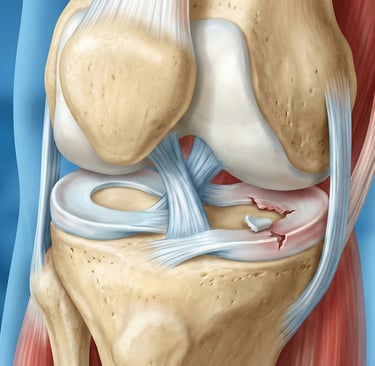

Kova Sapı Menisküs Yırtığı — Nedir?

Menisküsün uzunlamasına yırtılarak orta kısma (eklem içine) yer değiştirmesidir. Adını, yer değiştiren parçanın kova sapı formunu andırmasından alır.

Belirtileri

Ani şiddetli ağrı

Dizde kilitlenme (tam bükülememe veya düzleştirememe)

Şişlik ve boşluğa basma hissi

Tanı

Fizik muayene (McMurray, Thessaly testleri)

MR görüntüleme ile kesin tanı

Tedavi

Artroskopik tamir (dikme): Genç hastalarda öncelikli

Kısmi menisektomi: Tamir mümkün değilse yırtık parça alınır.

Konservatif tedavi: Çok küçük yırtıklarda veya cerrahi uygun değilse dinlenme + buz + fizyoterapi

Kilitli dizde acil müdahale gerekebilir.